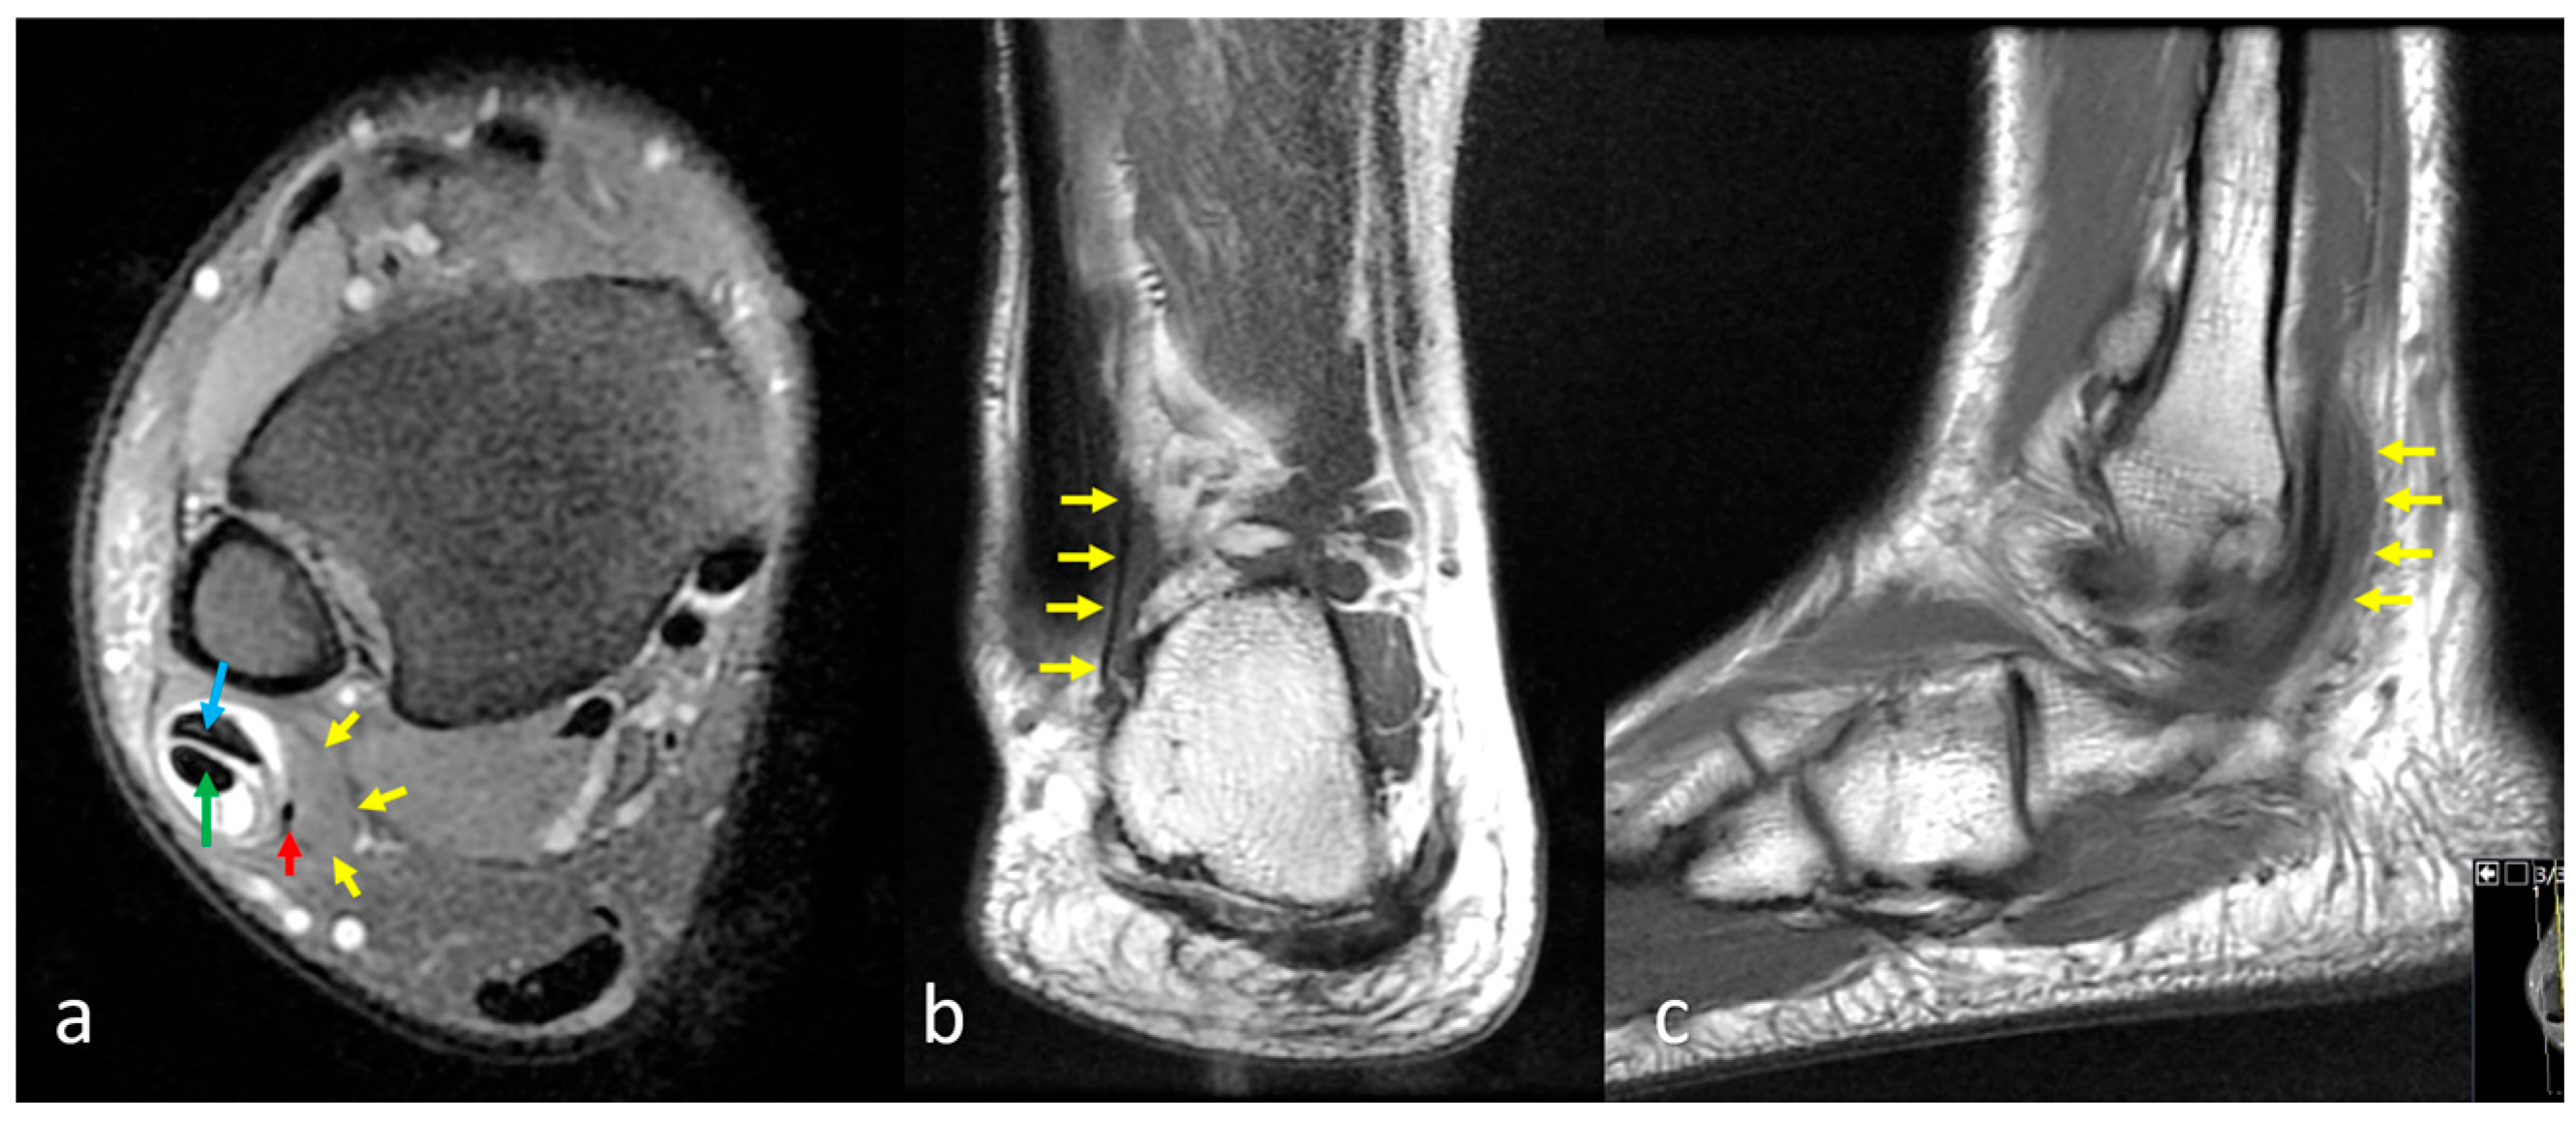

2.3. Assessment of the Peroneus Quartus Muscle and Peroneal Pathologies

2.4. Definitions of Peroneal Tendon Pathologies